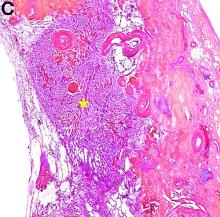

A 68-year-old woman, asymptomatic, with no medical history, underwent an abdominal computed tomography scan in a traumatic context. An enhanced series (Figure A) revealed a 4-cm cystic mass with tissue and calcified rim components located under the left liver (Figure A, arrow) inside the ligamentum teres. The lesion was supplied by a left hepatic artery branch. The frontal view showed the mass drainage into the left external iliac vein through a long pedicle (the umbilicus vein connected to the left inferior epigastric vein) (v).